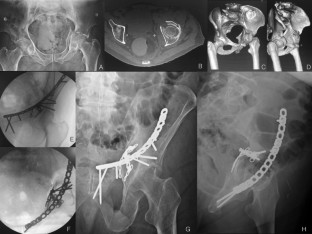

Fig. 1